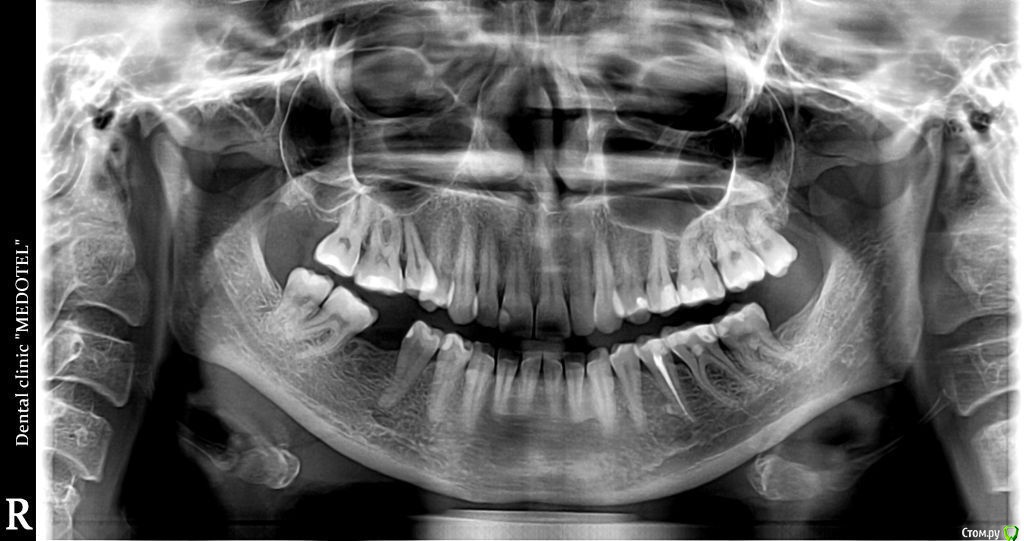

Александра_85 Опубликовано 12 марта, 2015 Поделиться Опубликовано 12 марта, 2015 (изменено) Здравствуйте, собираюсь сделать имплантацию 6 нижнего зуба справа.Удален этот зуб был 4 года назад, кость довольно сильно ушла.Мой имплантолог советует кость не наращивать, и установить тонкий импрант АльфаБио.Хотелось бы услышать ваше мнение.Во вложении ортопантограмма годичной давности, и свежее КТ по ссылкеhttp://www.fayloobmennik.net/4686662 Я не очень понимаю, как выложить срез.Сделала скрин, может по нему будет понятно Изменено 12 марта, 2015 пользователем Александра_85 Ссылка на комментарий

red_butler Опубликовано 12 марта, 2015 Поделиться Опубликовано 12 марта, 2015 (изменено) Вот.я бы имплантировал с одномоментной костной пластикой, однако существует современная тенденция - ставить импланты малого диаметра и ограничиваться пластикой десны Изменено 12 марта, 2015 пользователем red_butler 1 Ссылка на комментарий